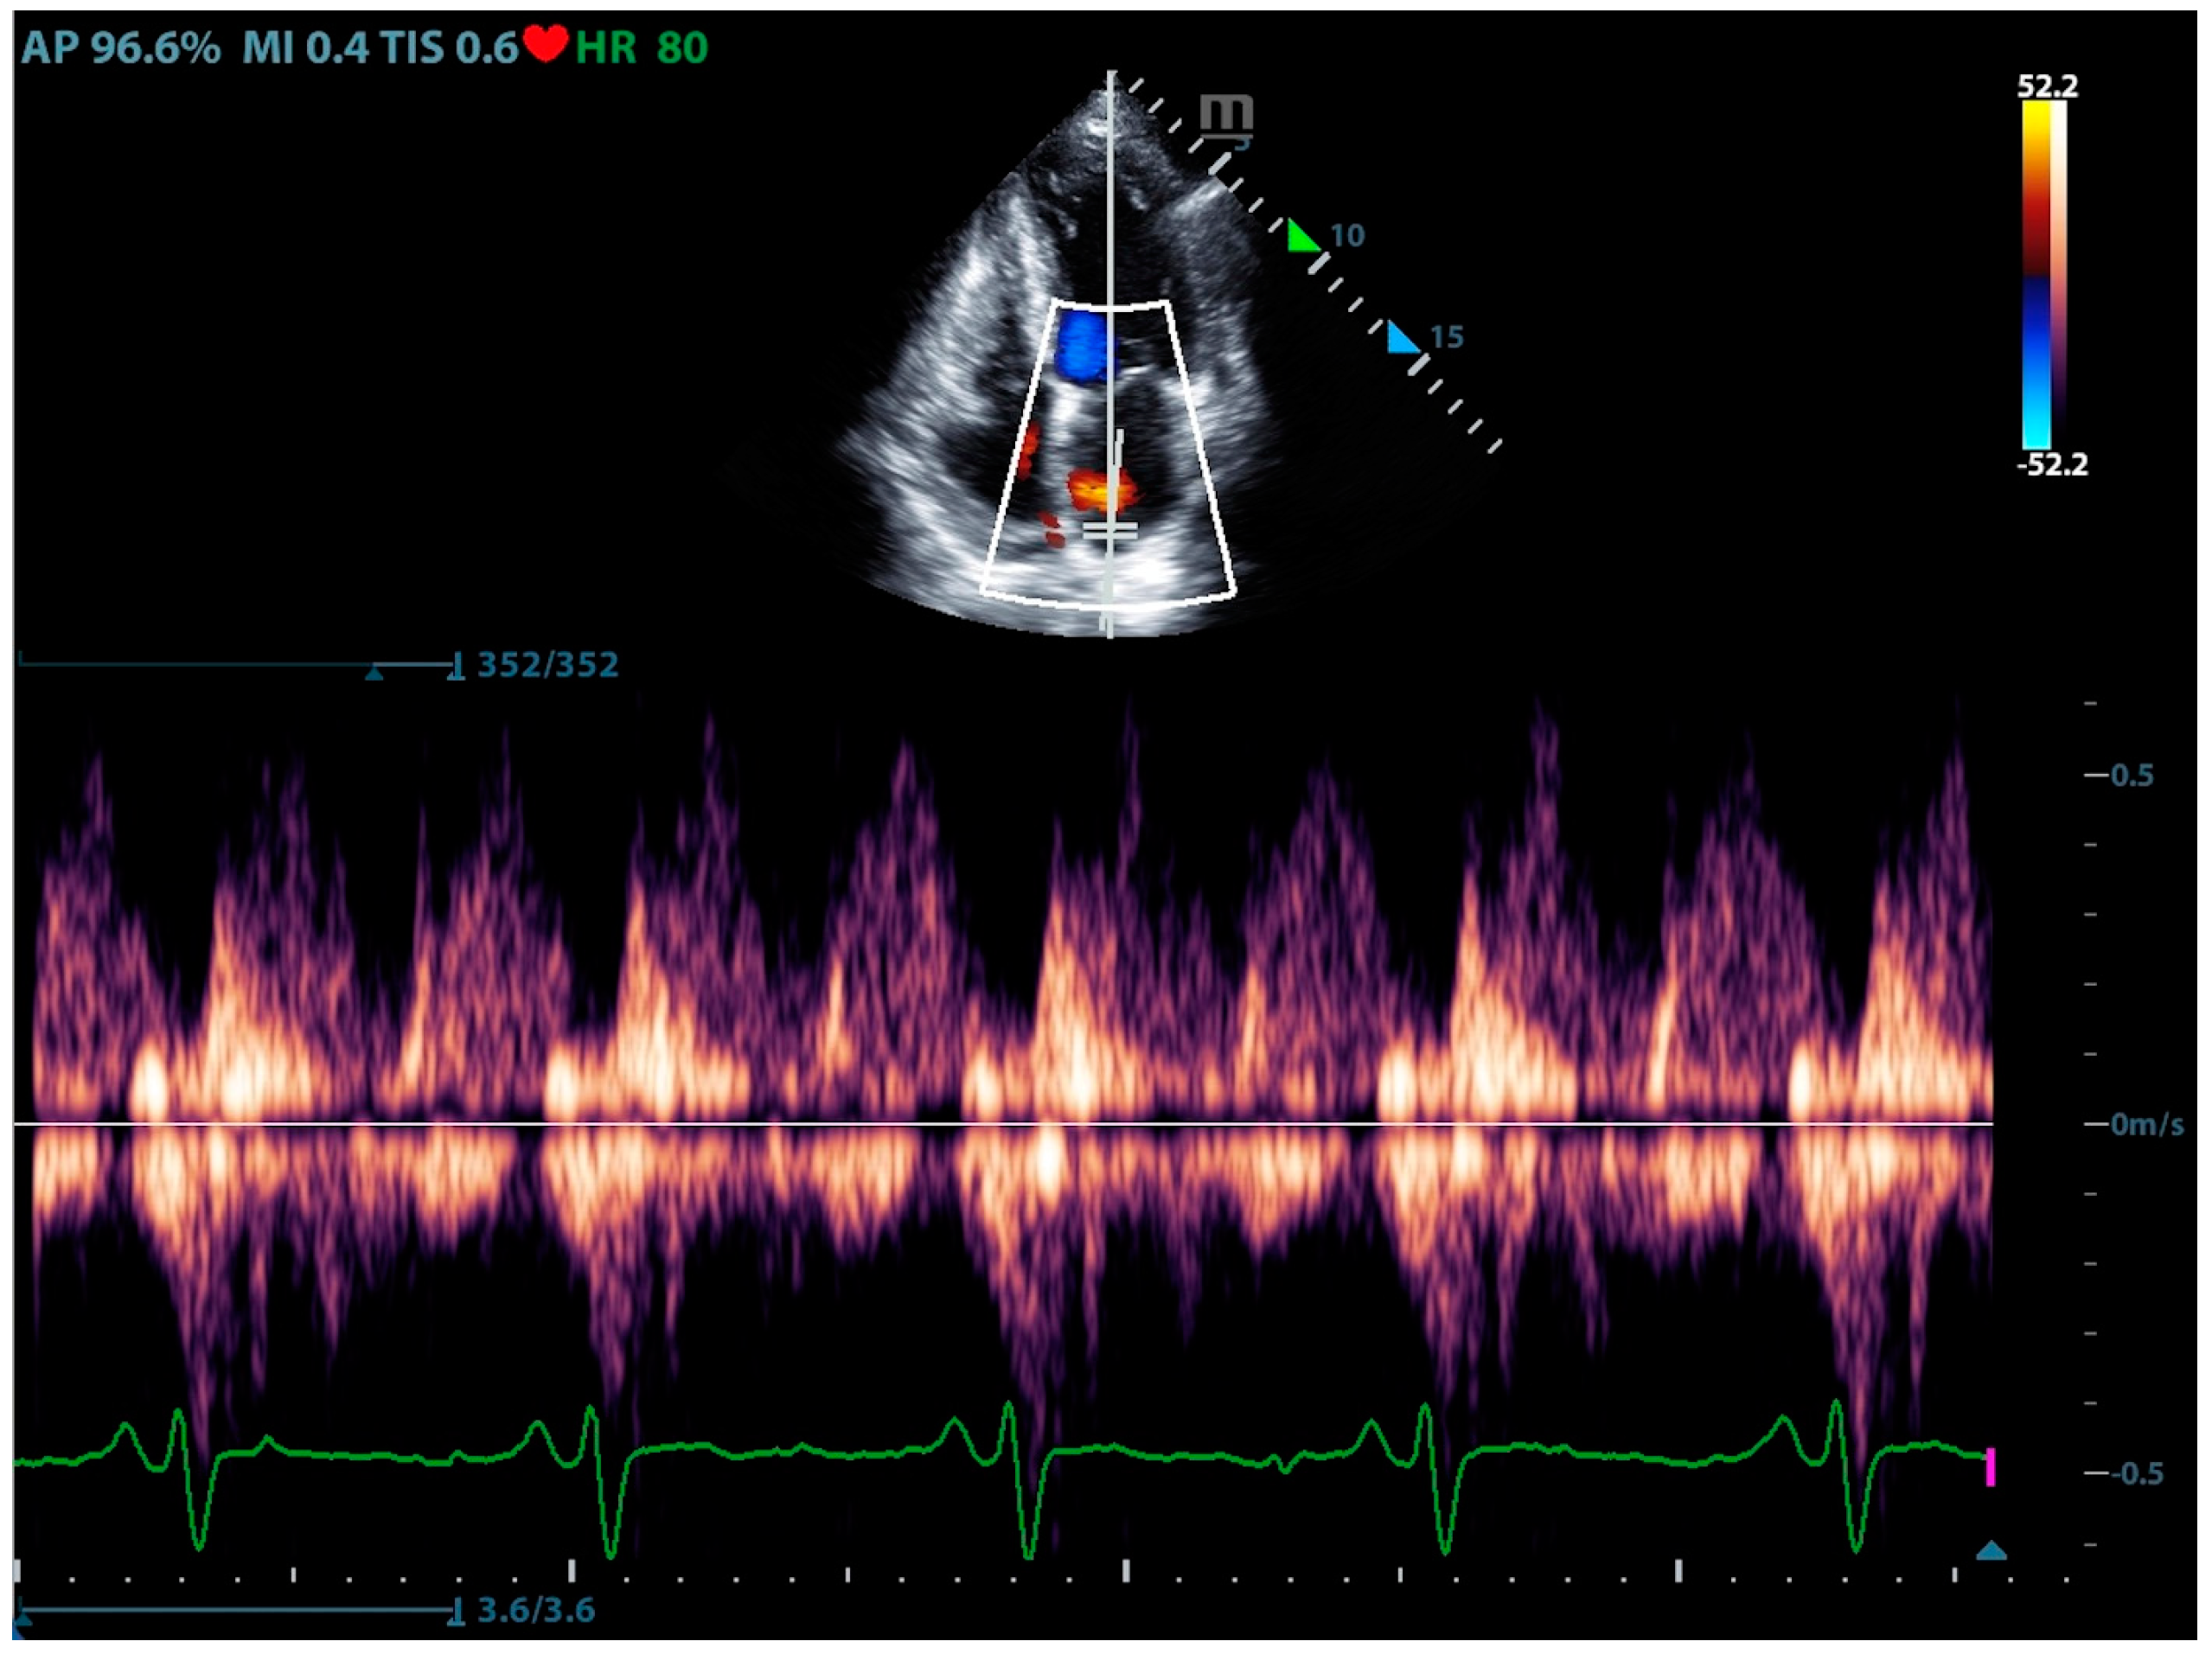

Physicians can assess pulmonary artery pressure quantitatively with point-of-care ultrasound. According to Bernoulli’s principle, the systolic pressure and diastolic pulmonary artery pressure can be estimated, respectively, by measuring the maximum regurgitation velocity of the tricuspid valve and the pulmonary valve. The maximum regurgitation velocity of the tricuspid valve (TVR Vmax) can be measured in the apical four-chamber view (Figure 6), and the maximum velocity of the pulmonary artery valve regurgitation (PVR Vmax) can be measured in the pulmonary artery long-axis view (Figure 7). Physicians can estimate pulmonary artery systolic pressure (PASP), diastolic pressure (PADP), and mean pulmonary artery pressure (mPAP) based on the ultrasound-measured TVR Vmax and PVR Vmax by the following formulas:

Figure 7.

The ultrasound measurement of the maximum velocity of the pulmonary artery valve regurgitation.

This can not only be used for the diagnosis of pulmonary hypertension but also for continuous and dynamic evaluation of pulmonary artery pressure [26]. It should be noted that the use of tricuspid regurgitation velocity to estimate pulmonary artery pressure with ultrasound Doppler has limitations. When the patient has severe tricuspid valve disease or severe right heart dysfunction, using the maximum tricuspid regurgitation velocity may underestimate the pulmonary artery pressure. Therefore, the evaluation of pulmonary hypertension should be combined with other ultrasound signs of the right ventricle, pulmonary artery, inferior vena cava, and right atrium.